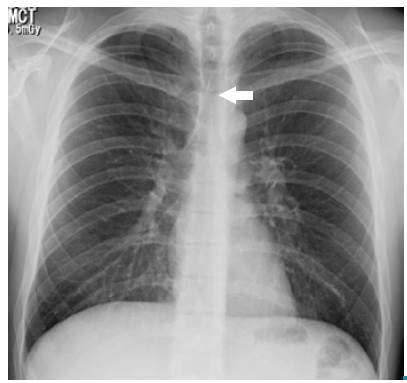

Based on the clinical and epidemiological characteristics, an acute respiratory infection of viral origin was considered; in addition, due to the presence of subcutaneous emphysema and alterations in pulmonary auscultation, spontaneous pneumothorax was suspected. Leukocytosis with neutrophilia and mild oxygenation disorder was found in the requested paraclinical exams (Table 1), while left chest and left supraclavicular soft tissues were observed on the chest radiograph (Figure 1).

PA chest x-ray: pneumomediastinum, delimitation of anatomical structures allowing a neat visualization of its contours (arrow).

Figure 1: PA chest x-ray: pneumomediastinum, delimitation of anatomical structures allowing a neat visualization of its contours (arrow).

Around 70% to 90% of SPM cases can be identified by chest X-ray 20. The presence of mediastinal air creates an interface with the anatomical structures that allows to visualize its contours neatly. Radiological signs depend on the quantity and location of the air 21: when it surrounds the vascular structures, the ring sign and the tubular artery sign appear. The delimitation of the inner and outer wall of the bronchus is possible due to the presence of intra and extraluminal gas, generating a double wall sign. The continuous diaphragm sign is caused by air posterior to the pericardium.

Other radiological signs include subcutaneous emphysema, radiolucent lines in the upper mediastinum, pneumoprepericardium, "Naclerio V", extrapleural air sign and, thymic wing sign caused by the delimitation of the thymus in children 16,21. Chest tomography delimits the extension of the pneumomediastinum, and provides information about its etiology and differential diagnoses 21,22.